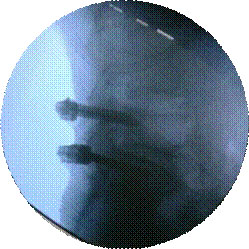

椎间孔镜微创术治疗腰椎间盘突出症

优点:损伤小、恢复快。

经皮穿刺椎体成形术

优点:微创,迅速解决老年骨质疏松性骨质疼痛。